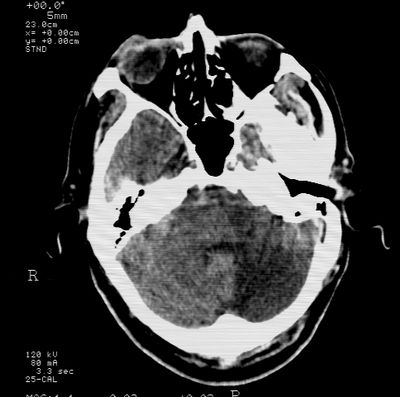

标题: CT21793:李x,男,62岁,头疼,头晕,家属否认有出血病史, [打印本页]

标题: CT21793:李x,男,62岁,头疼,头晕,家属否认有出血病史,

右基底节,海马并侵及右枕,左枕叶梗塞

支持右基底节,海马并侵及右枕,左枕叶梗塞。

支持右基底节,海马并侵及右枕,左枕叶梗塞。建议增强。

支持右基底节,海马并侵及右枕,左枕叶梗塞

多发梗塞,左小脑软化灶

多发性脑梗塞。

考虑多发脑梗塞,建议mri检查。